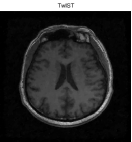

Besides the Shepp-Logan phantom image, we also tested Cameraman, Lena, Boat, Sailboat, as well as two brain images. In this experiment, we simply set and keep all other parameters unchanged. The original and the recovered images by TwIST and IADM are given in Figures 3 and 4, and detailed results including relative errors (RE), CPU time (Time), final objective function values (Obj), and the number of iterations (Iter) are presented in Table 2. It can be seen from Table 2 that IADM attained comparable or better image quality in less CPU seconds. For each test, IADM consumed more iterations while the CPU time is less because the per-iteration cost of IADM is much less than that of TwIST. Specifically, the per-iteration cost of IADM contains two matrix-vector multiplications and two FFTs, while TwIST needs to solve a TV denoising problem at each iteration. In addition, IADM always attained smaller function values. In summary, the comparison results indicate that IAMD performs favorably and can be competitive with the state-of-the-art algorithm TwIST.

| TwIST | IADM | ||||||||

|---|---|---|---|---|---|---|---|---|---|

| Images | Size | Iter | RE | Time | Obj | Iter | Re | Time | Obj |

| brain 1 | 52 | 14.01% | 34.25s | 4.7831e+002 | 208 | 13.64% | 20.41s | 4.5478e+002 | |

| brain 2 | 48 | 9.59% | 90.22s | 1.6397e+003 | 176 | 9.45% | 61.67s | 1.5665e+003 | |